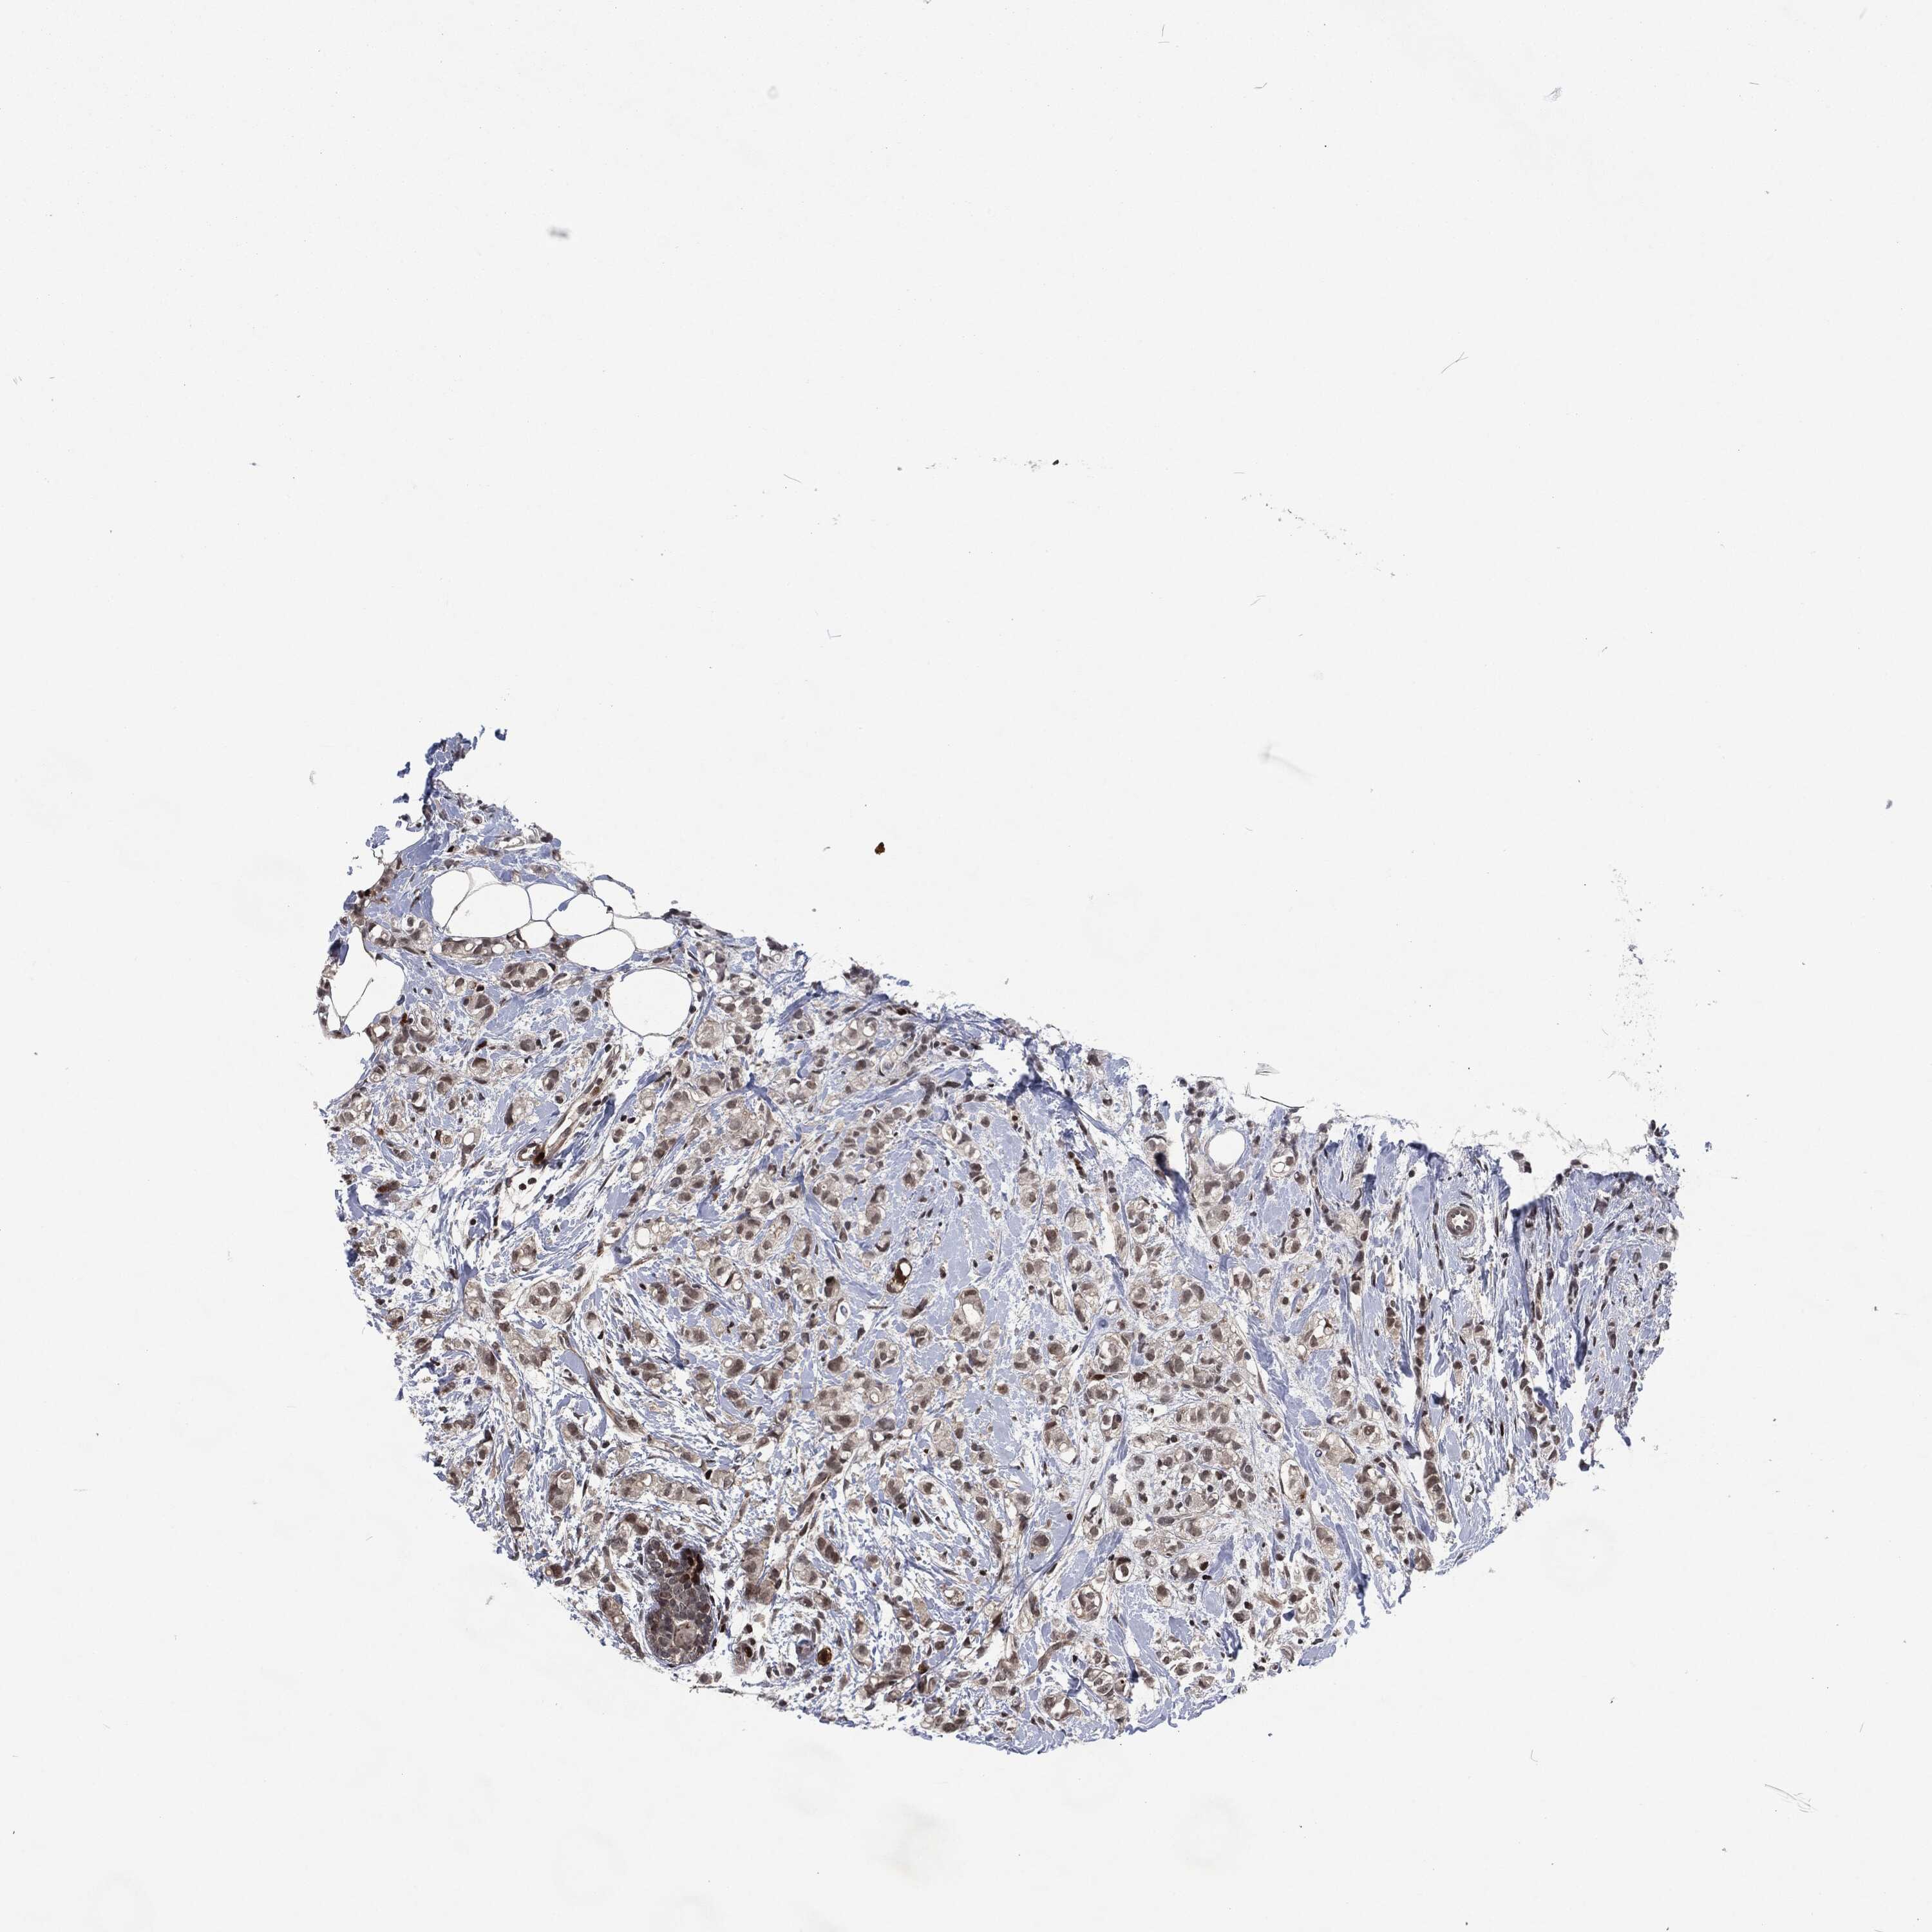

BRCA TCGA BRCA VALIDATION PROTEIN EXPRESSION

ANTIBODIES

AND

VALIDATION